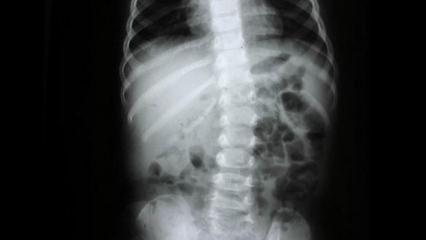

Hastanın durumunun son derece riskli olduğunu belirterek Prof. Dr. Köksal, “Zülbiye Hanım bize geldiğinde ileri derecede nefes darlığı vardı. Daha önce iki kez kalp ameliyatı geçirmişti ve bu kez triküspit kapağında ileri derecede kaçak vardı. 69 yaşında üçüncü bir kalp ameliyatı gerçekten çok ciddi riskler barındırır” dedi. Riskleri azaltmak için kapağı değiştirmek yerine tamir etmeyi tercih ettiklerini belirten Prof. Dr. Köksal, “Kapağın değiştirilmesi hem hayati riskleri artırır hem de hastanın ömür boyu daha yüksek doz kan sulandırıcı kullanmasına neden olur. Bu da ciddi kanama riskleri doğurur” diye belirtti.

“MADE IN TÜRKİYE” YÖNTEMİYLE TAMİR

Uygulanan yöntemin Türkiye’de geliştirildiğini vurgulayan Prof. Dr. Köksal, “Hastamızın triküspit kapağını, kendi geliştirdiğimiz ve ‘Made in Türkiye’ ismini verdiğimiz mitralizasyon yöntemiyle tamir ettik. Ayrıca ameliyatı sağ koltuk altından, endoskopik yöntemle ve kalbi durdurmadan gerçekleştirdik” diye konuştu. Bu yöntemin özellikle ileri yaş ve daha önce kalp ameliyatı geçirmiş hastalar için büyük avantaj sağladığını belirten Prof. Dr. Köksal, sözlerini şöyle tamamladı: “Küçük kesi, kalbi durdurmadan ameliyat ve kapak tamiri; teknolojinin bize sunduğu üç büyük avantaj. Yaşı kaç olursa olsun, her hastaya özel planlama yapıyoruz. En çok faydayı da bu hasta grubu görüyor.”